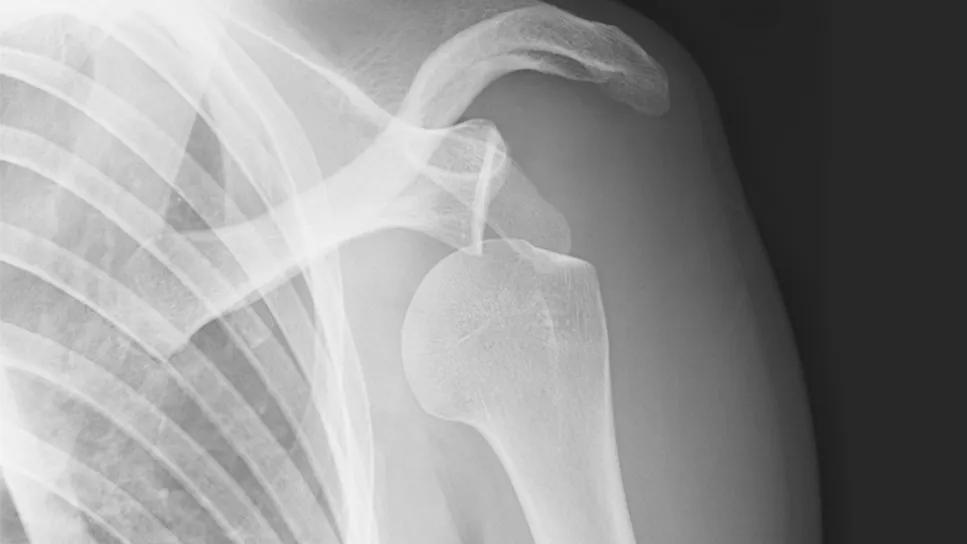

X-rays of total shoulder replacement

Diagnosis and Implant Type Drive Patient Outcomes in Shoulder Replacement Surgery

Conventional arthroplasty performs better than reverse arthroplasty for patients with an intact rotator cuff